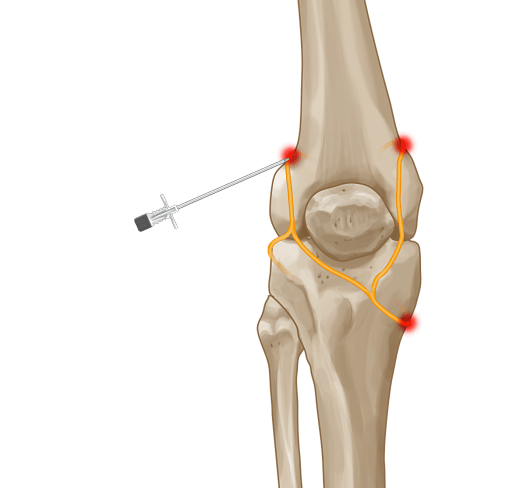

Knee joint Radiofrequency Neurectomy MIPSI

What is the procedure of Knee joint Radiofrequency neurectomy?

Knee joints are supplied by articular branches called as Genicular nerves. There are 4 genicular nerves around the knee joint

• Superomedial genicular nerve

• Superolateral genicular nerve

• Inferomedial genicular nerve

• Inferolateral genicular nerve

Knee joint Radiofrequency neurectomy is an advanced procedure which involves a precise identification of these articular branches( nerves supplying only the joint ) with the help of sensory and motor stimulation and then targeted ablation of these nerves using Radiofrequency current. Extreme caution is taken to spare the main sensory and motor nerves and only target the articular branches supplying the joint. Inferolateral genicular nerve is spared in this procedure because of its proximity to Common peroneal nerve whose inadvertent lesion can cause foot drop in the patients.